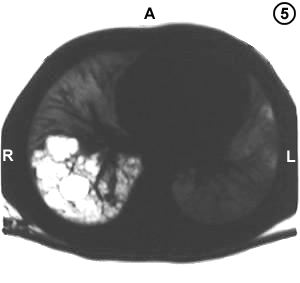

Corte Tomográfico " 5 "

El mismo Corte tomografico 3:

Parenquima pulmonar de aspecto normal excepto el lóbulo inferior derecho. Resolución tomografica para demostrar las cavidades quísticas que ahora se observan blancos en el parenquima pulmonar mas oscuro.